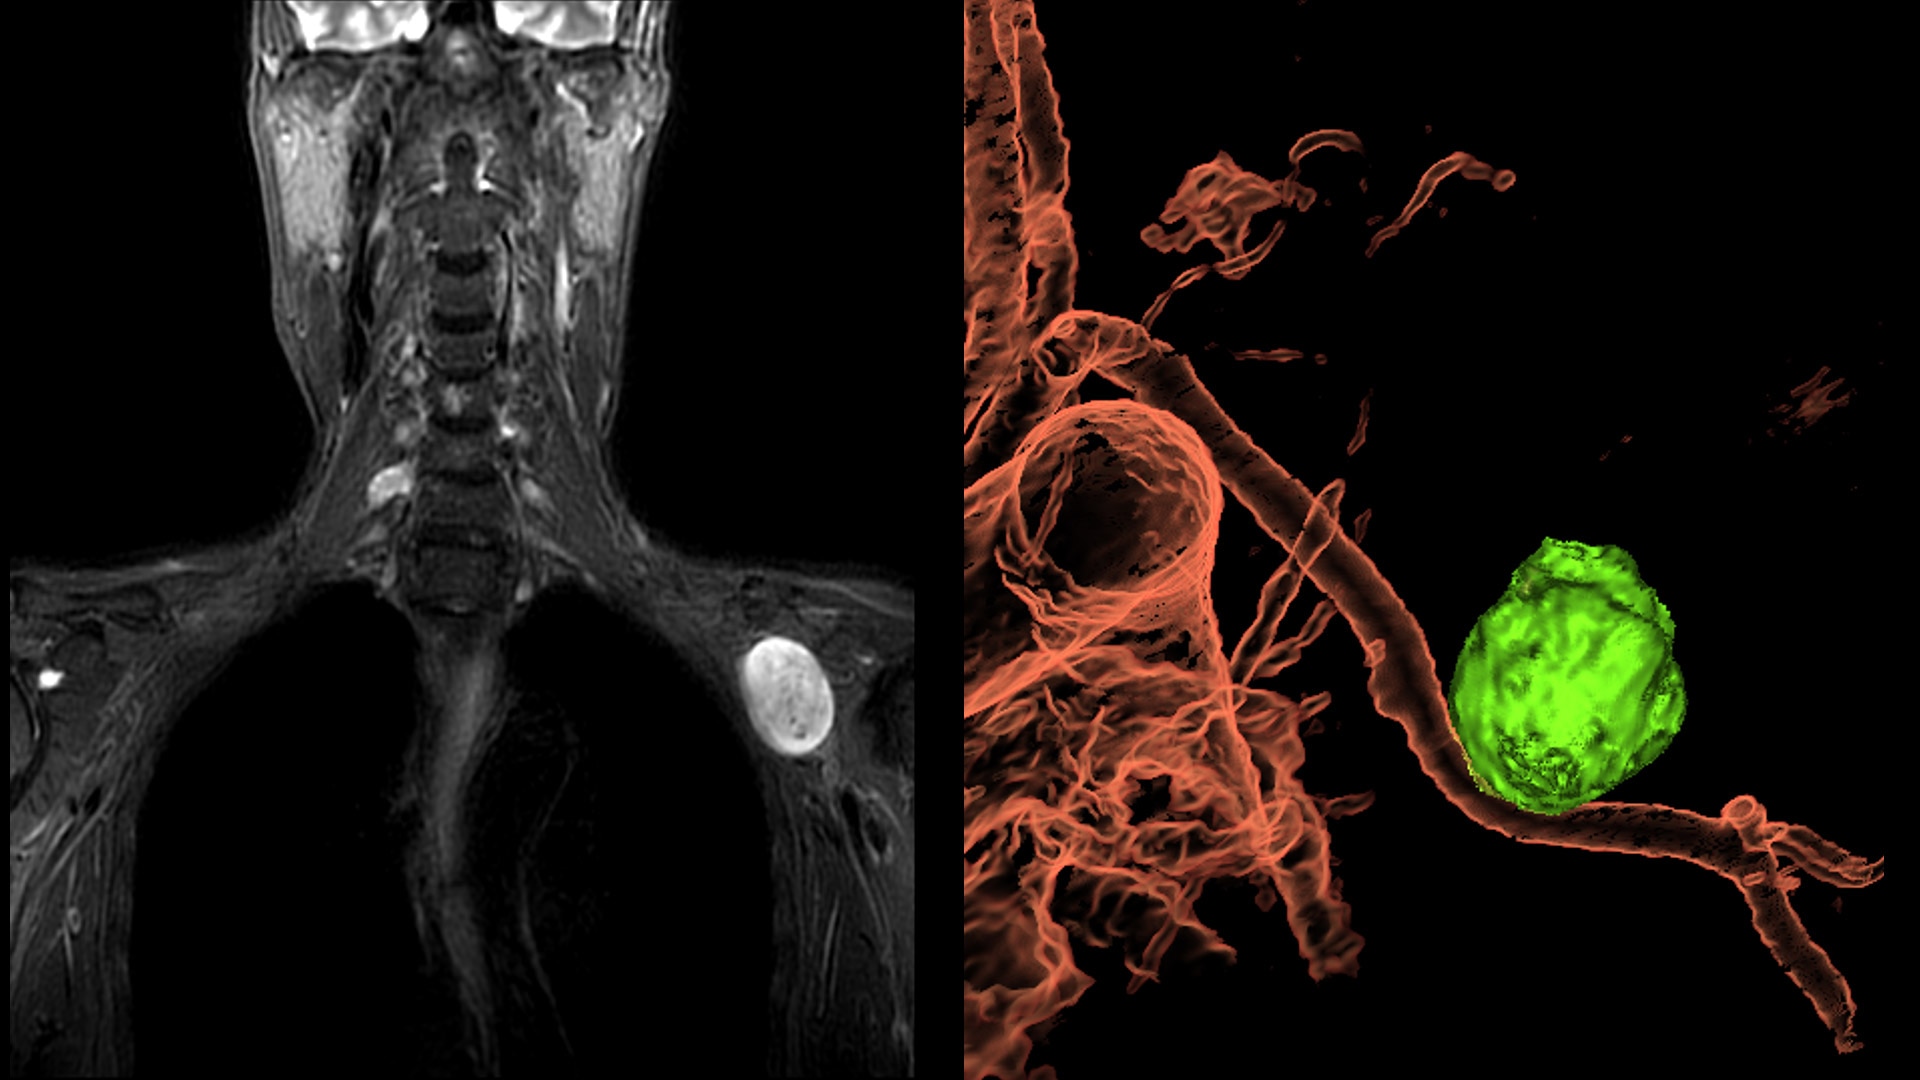

Clinical excellence

Coil flexibility makes it easier to get closer to the patient, providing more coverage compared to other coils